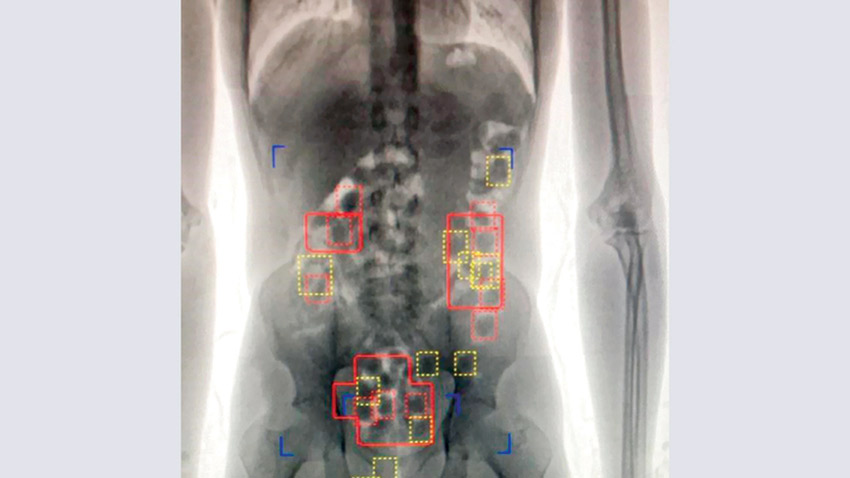

وتعود تفاصيل الواقعة عندما حضر المتهم إلى مملكة البحرين عبر مطار البحرين الدولي قادمًا من بلده الآسيوي وعند مروره بالمنطقة الجمركية اشتبه فيه الشاهد الاول وعليه قام بتفتيشه ولم يعثر على شيء وبسؤاله عن حيازته لأية ممنوعات أنكر إلا أن ملامحه كان يبدو عليها الارتكاب، حيث أمر ضابط الجمارك بتحويله إلى غرفة جهاز الأشعة وبالعرض عليه لوحظ وجود أشكال دائرية بداخل أحشائه مشتبه في أنها كبسولات مخدرة فتم تحويله إلى مكتب إدارة مكافحة المخدرات.

وبسؤال المتهم أقر بابتلاع كبسولات تحتوي على المواد المخدرة قاصدًا تهريبها الى مملكة البحرين وعليه تم تحويله الى مستشفى وزارة الداخلية وقام بإنزال عدد من الكبسولات على دفعات في اثناء مراقبة عملية إنزال الكبسولات حتى بلغ مجموع الكبسولات 84 كبسولة.